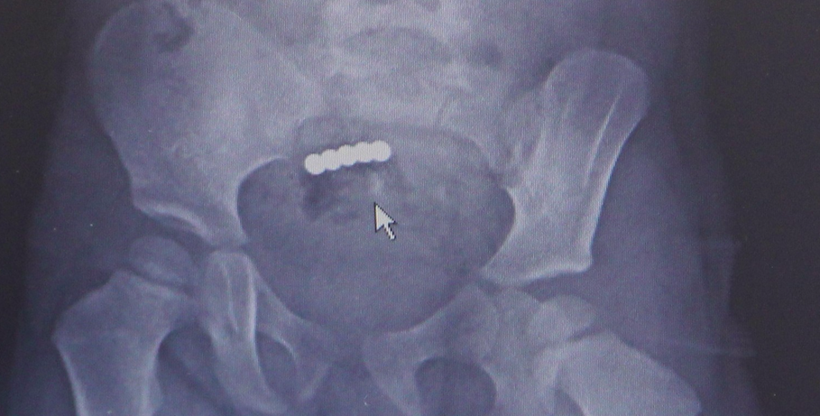

İzmir’in Aliağa ilçesinde yaşayan iki çocuk sahibi muhasebeci Nurdan (38) ve Makine Mühendisi Ali Güler (39) çifti, oğulları Mete’ye “Zeka küpü” diye satılan, manyetik mıknatıslardan oluşan oyuncak aldı. Geçtiğimiz 6 Mart’ta ağabey Mete bu oyuncakla oynarken ona kardeşi Cemre de katıldı. Mete, babasına Cemre’nin ağzına mıknatıs götürmüş olabileceğini söyledi. Cemre’nin de “yuttum” demesi üzerine çift kızlarını gözlem altına aldı. Bir tane mıknatıs yutmuş olabileceği ihtimali üzerine Cemre’nin dışkı yoluyla bu mıknatısı çıkarabileceği düşünüldü, ancak ertesi akşamüstü Cemre’nin kusmaya başlaması ve karnının ağrıdığını söylemesi üzerine aile hiç zaman kaybetmeden İzmir’e geldi ve Kent Hastanesi’ne başvurdu. Çekilen röntgende Cemre’nin birden fazla mıknatıs yuttuğu saptandı. Hemen ameliyata alınan Cemre’nin bağırsaklarından 5 mıknatıs çıkarılırken, bağırsağının delindiği belirlendi. Bağırsağının 10 santimetre kadarlık bir bölümü alınan Cemre, daha 2,5 yaşında ameliyat masalarıyla tanışırken, 5 gün yattığı hastaneden şifayla taburcu oldu.

İki buçuk yaşında bir çocuk için bağırsak tıkanıklığı ve delinmesi çok ağır tablolardır. Yetişkinler için de öyle; ama 2,5 yaşında olunca çok daha kötü şekilde önümüze geliyor. Ameliyatta tahmin ettiğimiz gibi 4 mıknatıs bir bağırsakta, 1 mıknatıs diğer bağırsakta dururken bunlar birbirlerini bulmuşlar. Çok da güçlü mıknatıslar olduğu için aradaki iki bağırsak duvarı zamanla eriyip mıknatısların birbirine bağlanmasına neden olmuş. Bir bağırsak kısmında 3 delik vardı. Yaklaşık 10 santimetre kadar bağırsağı çıkarmak durumunda kaldık, diğer tarafta ise bağırsaktaki deliği onardık” dedi.